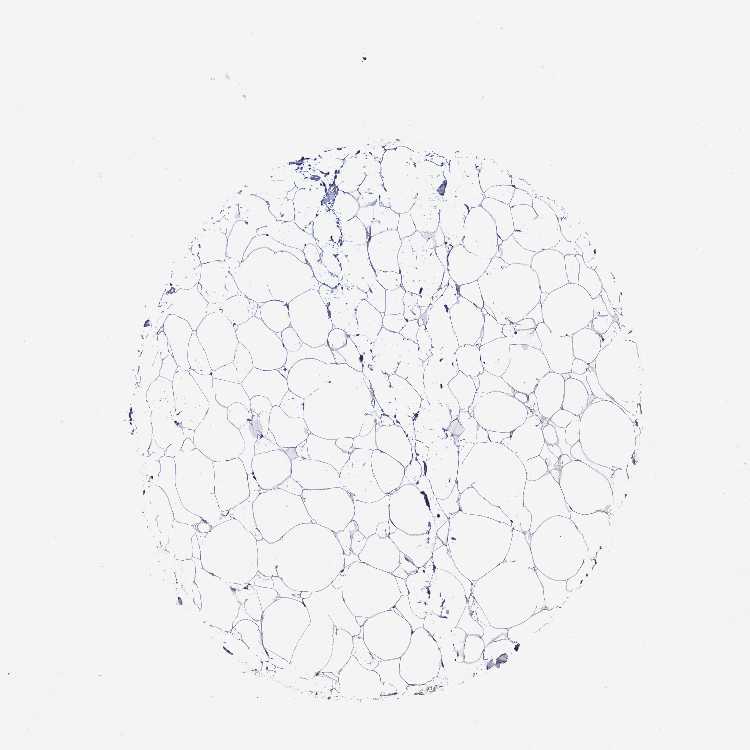

SOFT TISSUE 1 - Antibody stainingi

Antibody staining in the annotated cell types in the current human tissue is reported as not detected, low, medium, or high, based on conventional immunohistochemistry profiling in selected tissues. This score is based on the combination of the staining intensity and fraction of stained cells.

Each image is clickable and will lead to virtual microscopy that enables deeper exploration of all samples and also displays staining intensity scores, fraction scores and subcellular localization as well as patient and tissue information for each sample.

Antibody HPA043541

Chondrocytes Low

Fibroblasts Not detected